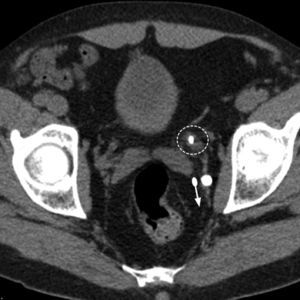

DiagnosisDirect visualization of the calculus is the main CT sign in RC and can usually be identified in most cases. On occasion, it can be difficult to see because of respiratory or metal devices adjacent to the lithiasis, because it is very small or because its composition is “CT-lucid”. The latter occurs with certain infective lithiases made up of proteinaceous material or in lithiases secondary to some antiretroviral drugs in HIV patients.53 When the calculus is located in the distal ureter, it can be difficult to differentiate from a phlebolith, especially if fine sections are not available. In this case the “halo” and “comet tail” signs are useful (Fig. 3). The former refers to the padding of soft parts around the lithiasis, caused by the edematous ureteral wall,54 and the latter, described as typical of phleboliths, consists of the observation of a tail of soft tissue density corresponding to the venous vessel.55 When it is not possible to differentiate them IV contrast in the excretory phase is necessary to be able to see the ureteral pathway.

Computed axial tomography without contrast of a patient with left RC. Two pelvic calcifications are identified. One of them corresponds to an obstructive distal ureteral lithiasis showing a discontinued circle (halo sign) formed by the edematous ureteral wall around the lithiasis. Another larger and posterior calcification is a phlebolith with the comet tail sign, corresponding to a posterior trail made up of the vessel where the phlebolith is (parallel to the arrow).